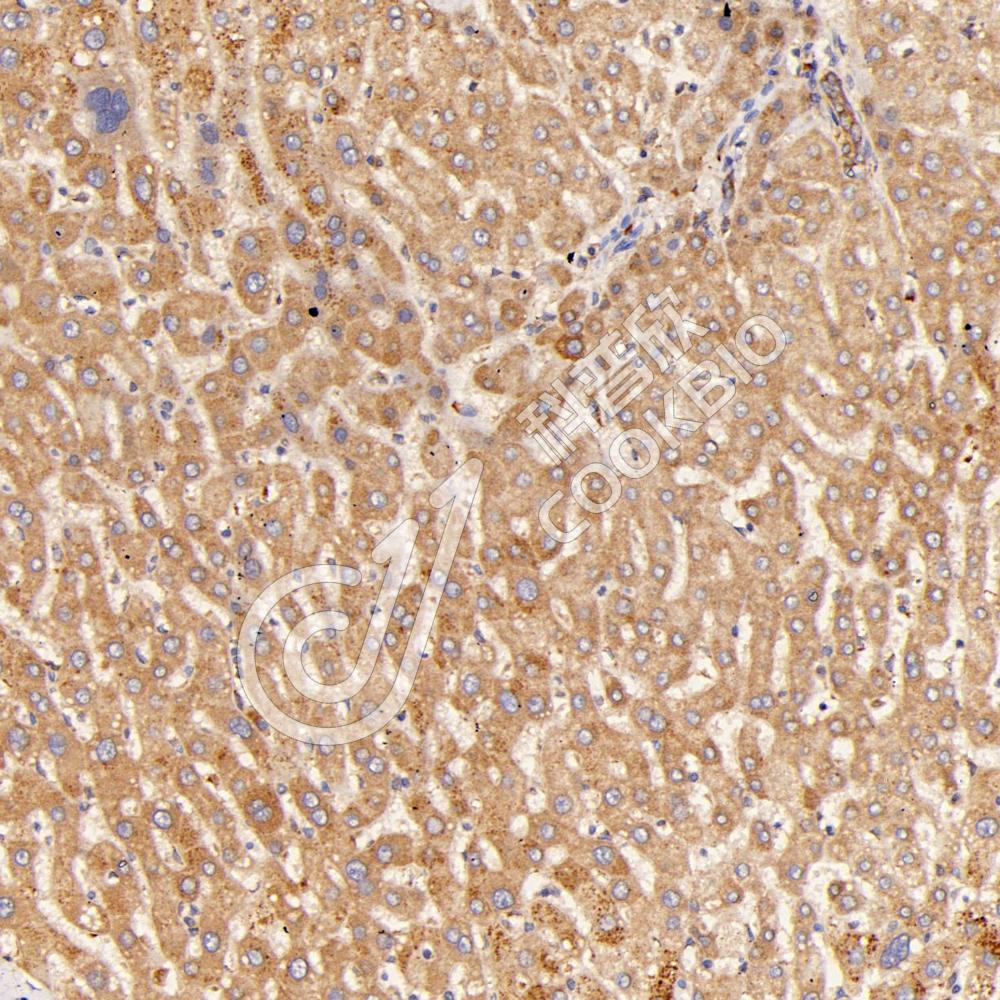

IHC检测Chromogranin A蛋白(货号 K1333948).

样品: 大鼠脑, 4%多聚甲醛 (货号KSG1101) 固定12-24小时.

抗原修复: 柠檬酸抗原修复液(干粉, pH 6.0) (KSG1201), 98℃, 20分钟.

—抗: 1: 2500稀释, 4℃ 孵育过夜.

二抗: S-vision免疫组化多聚二抗(山羊抗兔),即用型 (货号KB3906), 室温孵育20分钟.